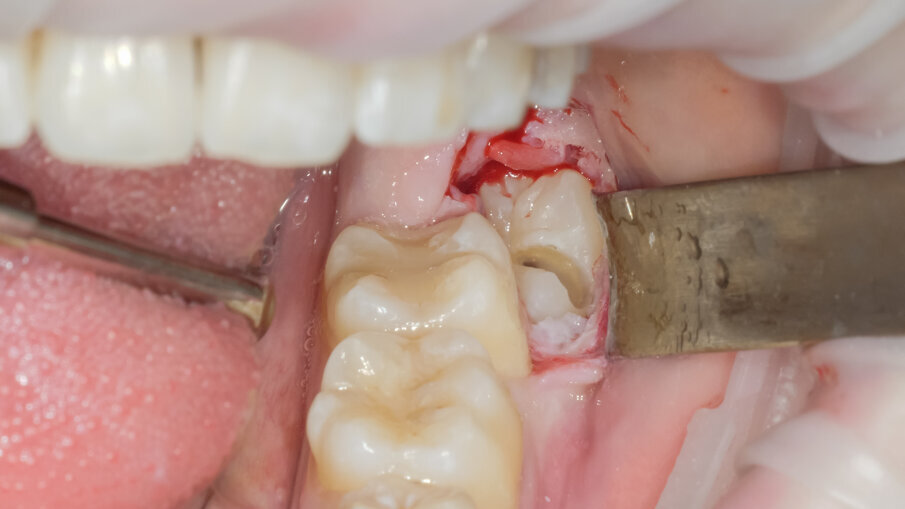

L’ostectomia di accesso per evidenziare la corona è stata praticata mediante inserto SLO-H. Questo inserto nasce per il disegno della botola ossea nel rialzo di seno laterale, ma per la sua forma e il forte potere tagliente risulta molto efficace anche nella ostectomia peridentale (Figg. 3, 4). Mediante fresa a fessura in carburo di tungsteno montata su manipolo diritto sotto costante irrigazione di fisiologica sterile si è proceduto alla fase di odontotomia verticale in modo da separare la porzione corono radicolare mesiale da quella distale (Fig. 5).

La scelta condivisa è quella di utilizzare la tecnologia piezolettrica per le fasi di odontotomia, solo nelle zone di difficile accesso o in prossimità di strutture anatomiche a rischio come il nervo alveolare inferiore. Per la fase di lussazione si è applicato il protocollo descritto da Fontanella utilizzando il nuovo inserto EXL1 (Figg. 6, 7). Questo inserto insieme agli altri due inserti lussativi (EXL2, EXL3) hanno la particolarità di sfruttare l’impulso piezoelettrico associato al movimento lussativo dell’inserto montato sul manipolo. La cavità residua è stata gestita rimuovendo i residui di sacco follicolare e detergendo il sito post estrattivo sfruttando l’effetto cavitazionale della tecnologia piezoelettirca (Fig. 8). Il lembo riposizionato è stato suturato con chiusura per prima intenzione con punti singoli riassorbibili 4/0 (Fig. 9). Al controllo post operatorio la ferita presentava una guarigione nella norma, e la paziente riferiva un post operatorio senza particolare gonfiore e con assunzione di antidolorifico solo nel primo giorno post chirurgico